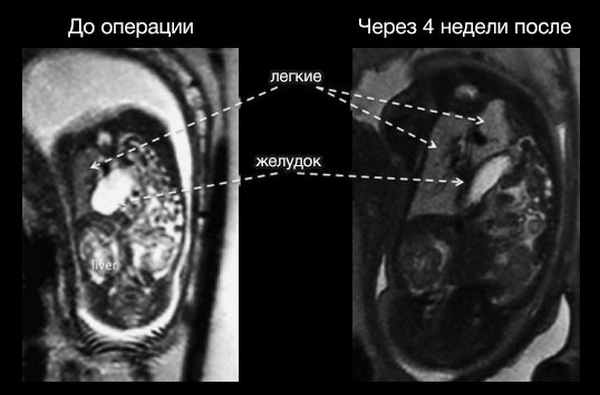

В течение четырех-восьми недель легкое усиленно развивается, значительно увеличивается в размере, вытесняя органы брюшной полости. Таким образом, одновременно достигается уменьшение гипоплазии легкого и вправление грыжевого содержимого.

Рисунок 4 | МРТ до проведения процедуры (слева) и спустя 4 недели после установки баллона (справа).

Преимущество метода баллонной окклюзии трахеи перед постнатальным оперативным вмешательством подтверждено многими исследованиями. Отмечается высокая выживаемость по сравнению с «выжидательной» тактикой; процент легочной гипоплазии среди детей с дородовым вмешательством ниже, а оценка по шкале Апгар на 1 и 5 минуте выше, чем у детей без коррекции порока. Учитывая, что врожденная диафрагмальная грыжа связана с высоким уровнем неонатальной смертности, данный метод коррекции является наиболее перспективным.